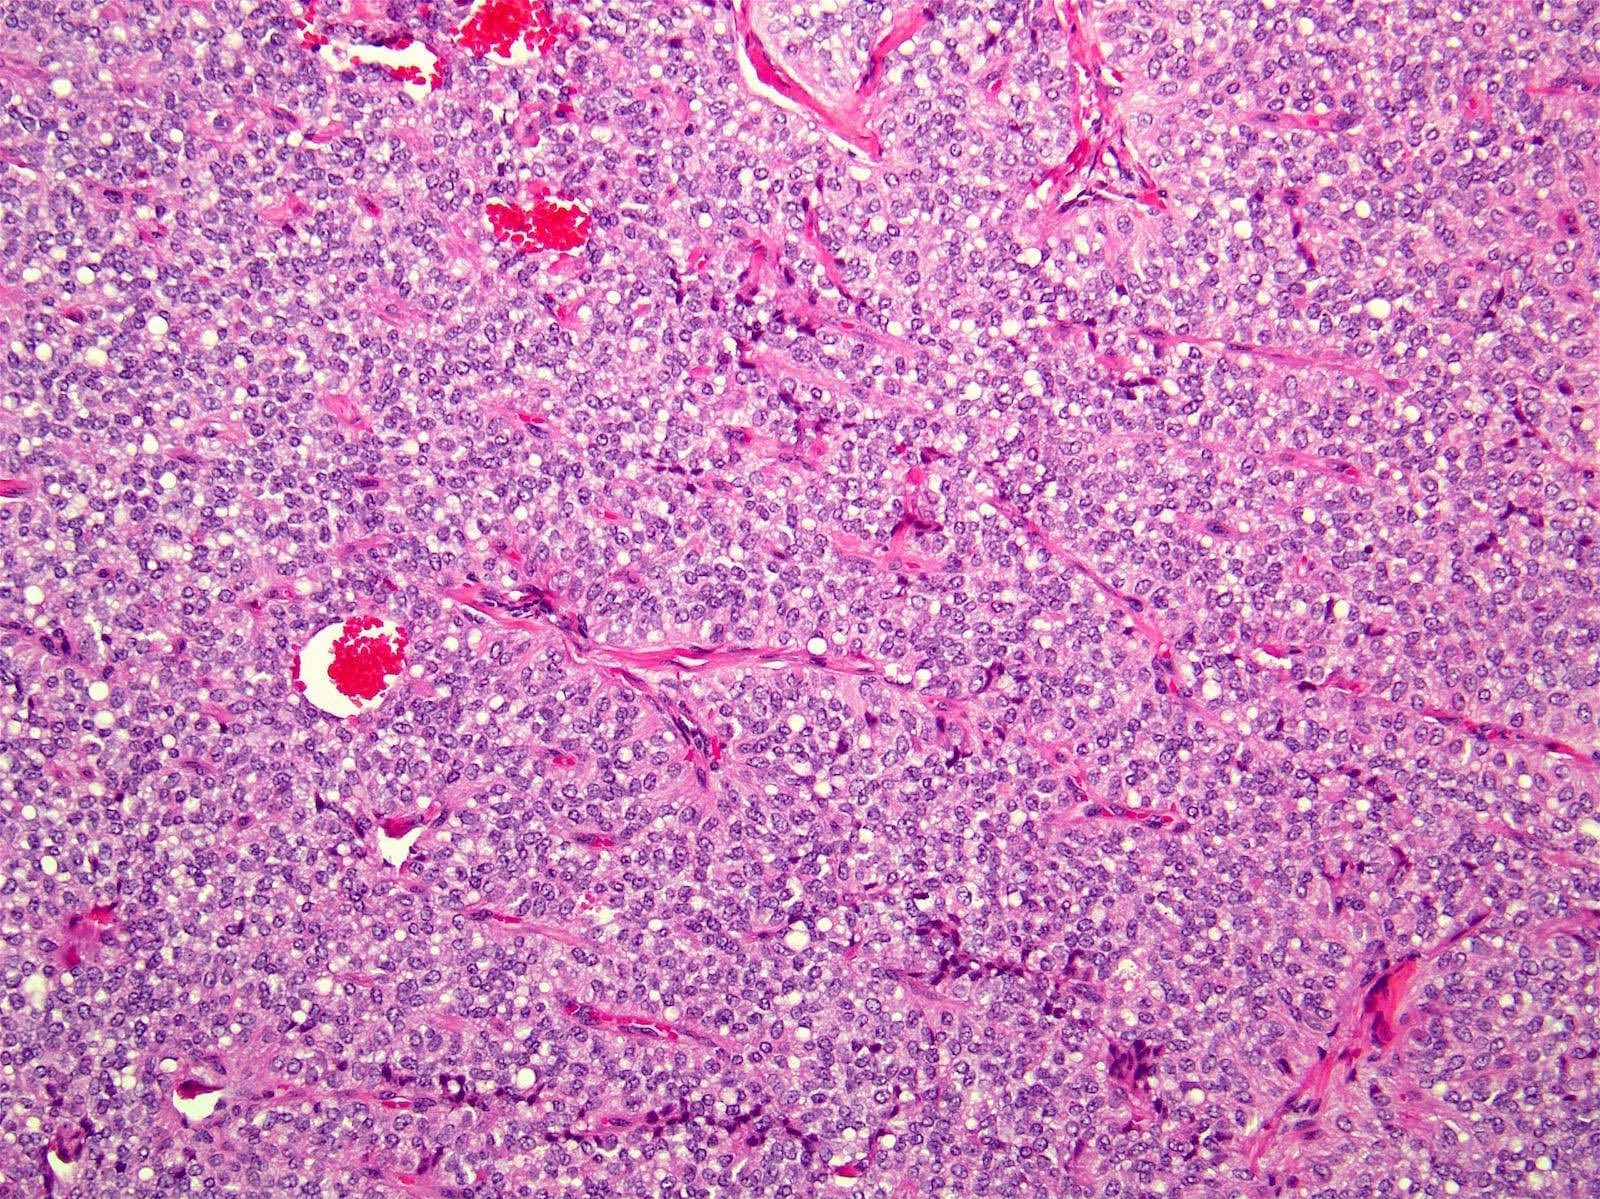

Microscopic (histologic) description

- Tumors are heterogeneous, with variable admixture of solid and pseudopapillary areas

- Solid areas are comprised of uniform cells admixed with capillary sized blood vessels

- Pseudopapillae are formed due to tumor cells getting detached from blood vessels forming fibrovascular stalks or rosette-like structures (Arch Pathol Lab Med 2020;144:829)

- Stroma usually shows various degrees of hyalinization or evidence of degeneration, such as hemorrhage, foamy macrophages, calcification and cholesterol clefts

- Tumor cells usually have a moderate amount of eosinophilic cytoplasm with intracytoplasmic hyaline globules (PAS+ and diastase resistant, positive for alpha-1-antitrypsin) and perinuclear vacuoles (Am J Surg Pathol 2011;35:981)

- Relatively uniform nuclei with finely textured chromatin, inconspicuous nucleoli and characteristic longitudinal grooves

- Variants include clear cell, oncocytic and pleomorphic

- Rare mitotic figures

- Although grossly well circumscribed, microscopic finding of infiltration to the surrounding pancreatic tissue is not uncommon

- Rare cases of highly aggressive behavior; histological features in those cases included diffuse growth pattern, extensive necrosis, significant nuclear atypia, high mitotic count (35 - 70/50 high power fields) or sarcomatoid features (Am J Surg Pathol 2005;29:512)

Microscopic (histologic) images

Contributed by Monika Vyas, M.D., Omid Savari, M.D. and Raul S. Gonzalez, M.D.